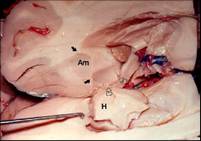

Amygdala

• Amygdala [ah-MIG-dah-la] two almond-shaped neural clusters linked to emotion of fear and anger.

The Limbic System

• Limbic System a doughnut-shaped system of neural structures at the border of the brainstem and cerebrum, associated with emotions such as fear, aggression and drives for food and sex. It includes the hippocampus, amygdala, and hypothalamus.